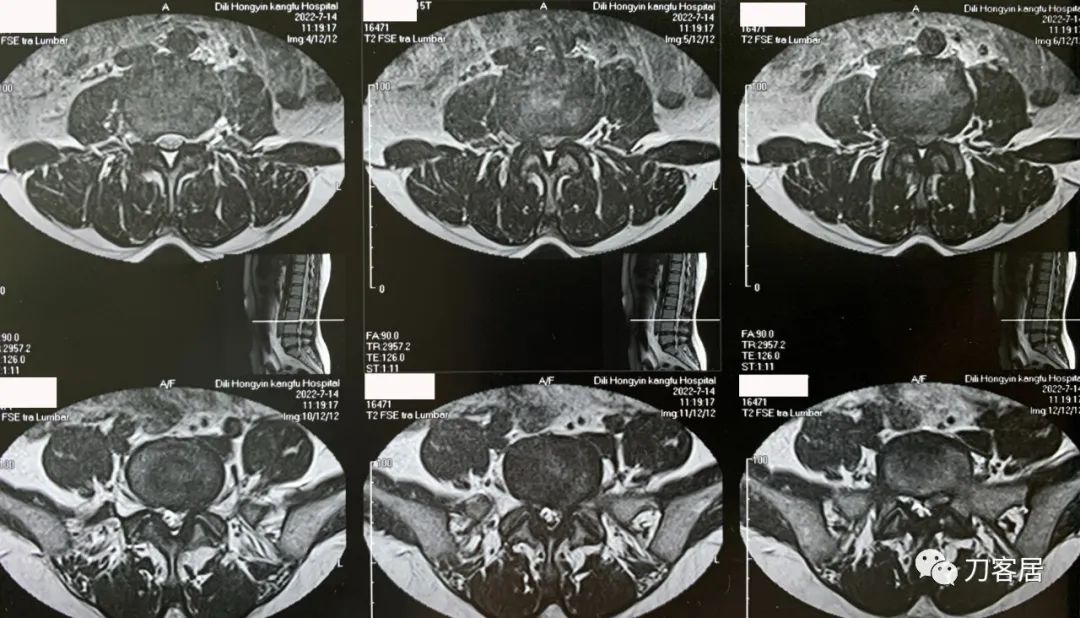

图1. 20220714外院腰椎MRI1,提示腰3-5椎间盘突出,椎管狭窄。

图2. 20220714外院腰椎MRI2,提示腰3-骶1椎间盘突出,椎管狭窄。

图3. 20220714外院腰椎MRI3,提示腰4-5椎间盘突出,椎管狭窄。

图4. 20220714外院腰椎MRI4,提示腰3-4椎管狭窄,腰5骶1椎间盘突出,左旁侧型。